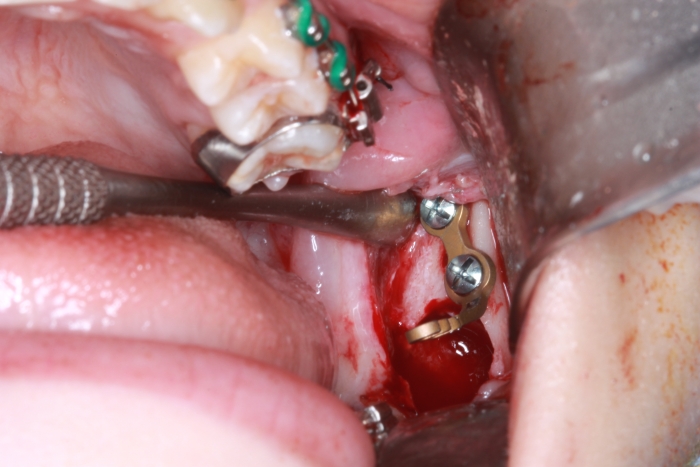

Extração dos 4 terceiros molares   - Instalação de placas de ancoragem - Clínica Cliniface

Extração dos 4 terceiros molares - Instalação de placas de ancoragem